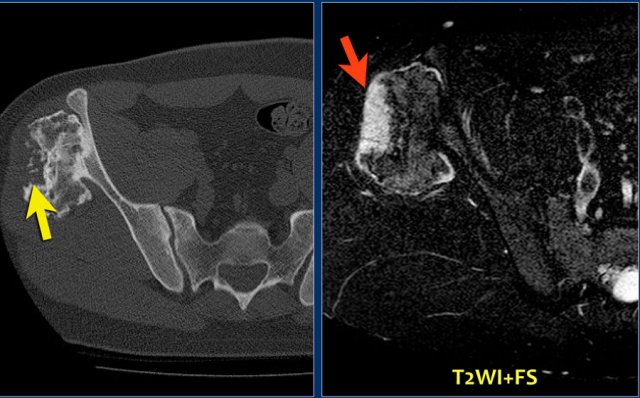

Here a patient with multiple osteochondromas.

Follow up is necessary because of an increased risk of malignant degeneration.

Continue with CT and MR.

CT:

• Large osteochondroma arising from the iliac bone.

• The central defect and punctate calcifications are highly suspicious for malignant progression to a peripheral chondrosarcoma.

MRI:

• The defect is filled with a large cartilage cap with high SI.

• This is diagnostic for the diagnosis chondrosarcoma